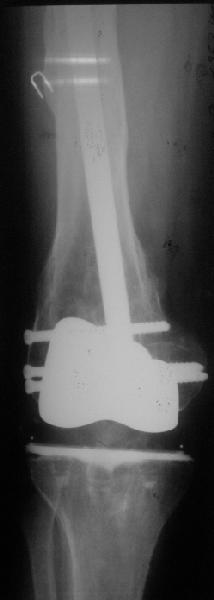

Видимо, самое "модное" на сегодня - малоинвазивный остеосинтез пластиной с угловой стабильностью. Распространенный вариант и закрытый интромедуллярный остеосинтез ретроградно. Хотя у нас было бы сделано антеградно - лешево и сердито, действительно малоинвазивно, в сустав не надо влезать. Нет риска прорезания порозной кости с миграцией в сустав, что возможно при ретроградном - гвоздь вводится через вырез в бедреннм компоненте, туда же может и вывалиться. А антеградный - упрется в протез. Как раз вчера заходил больной через полтора года после такой операции. Снимки в приложении.

Учитывая высокую вероятность уже имеющейся нестабильности тибиального компонента и развившуюся при травме нестабильность бедренного, имеет смысл удаление обоих компонентов, реэндопротезирование конструкцией, имеющей возможность интрамедуллярного закрепления на длинном стержне (NexGen LCCK (Zimmer), AGC (Biomet), RT-Solution (Plus Endoprosthetik) и т.п.), параллельно выполнить остеосинтез винтами, серкляжами, пластиной - что окажется лучше, решить во время операции.

Мне представляется следующее: Если дистальный отдел бедра расколот и в сагиттальной и во фронтальной плоскостях, как видно на рентгенограммах, и при этом есть смещение отломков относительно друг друга и бедренного компонента эндоаротеза, разве от может оставаться стабильным? В случае отсутствия проблем с тибиальным компонентом, можно было бы надеяться только на остеосинтез и стабилизацию, но если предполагается ревизия в ближайшие месяцы/год, то не лучше ли за один раз решить несколько проблем?